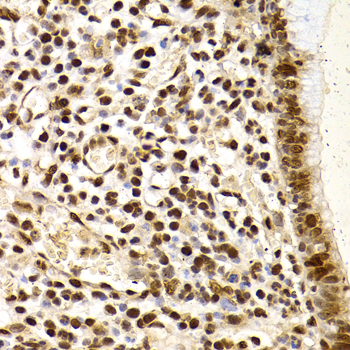

Immunohistochemistry of paraffin-embedded human B cell lymphoma using XRCC4 antibody at dilution of 1:200 (400x lens).